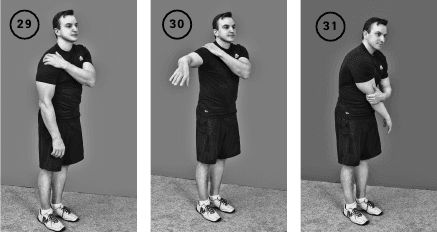

Упражнение «Помогаем плечу»

Исходное положение – стоя или сидя. Кисть левой руки кладем на правый плечевой сустав так, чтобы 2-4-й пальцы кисти оказались на дельтовидной мышце, ниже костного выступа плечевого сустава (акромеальный отросток лопатки).

Фаза изометрического напряжения: нажимаете кистью на плечо, а плечо отводите до прямого угла в сторону, либо на столько, на сколько позволяет объем движений. Удерживаем это положение изометрического напряжения 20–30 секунд.

Фаза растяжения: обхватываете левой кистью правое плечо чуть выше локтевого сустава и тянете плечо вниз и влево (ил. 29–31).